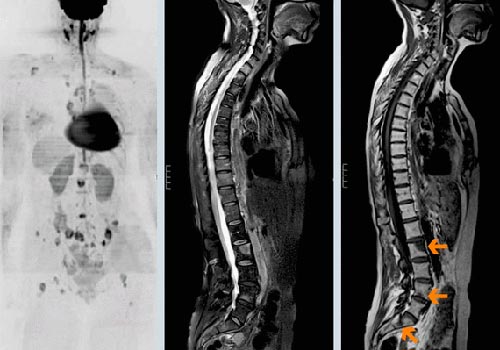

Для выставления окончательного диагноза проводится целый ряд обследований, в число которых входит УЗИ органов грудной клетки, брюшной полости, органов таза, компьютерная томография (КТ), магнитно-резонансная томография (МРТ), остеоденситометрия, рентгенография и скелетная сцинтиграфия.

Как выглядят метастазы в позвоночнике на МРТ?

Метастазы в телах позвонков на МРТ снимках видны неодинаково, поскольку все зависит от вида и количества патологического очага. Выглядят как темные пятна с четким или размытым контуром. Определяют на Т1 или Т2 взвешенных изображениях, которые позволяют получить гипо- или изоинтенсивный МР-сигнал.